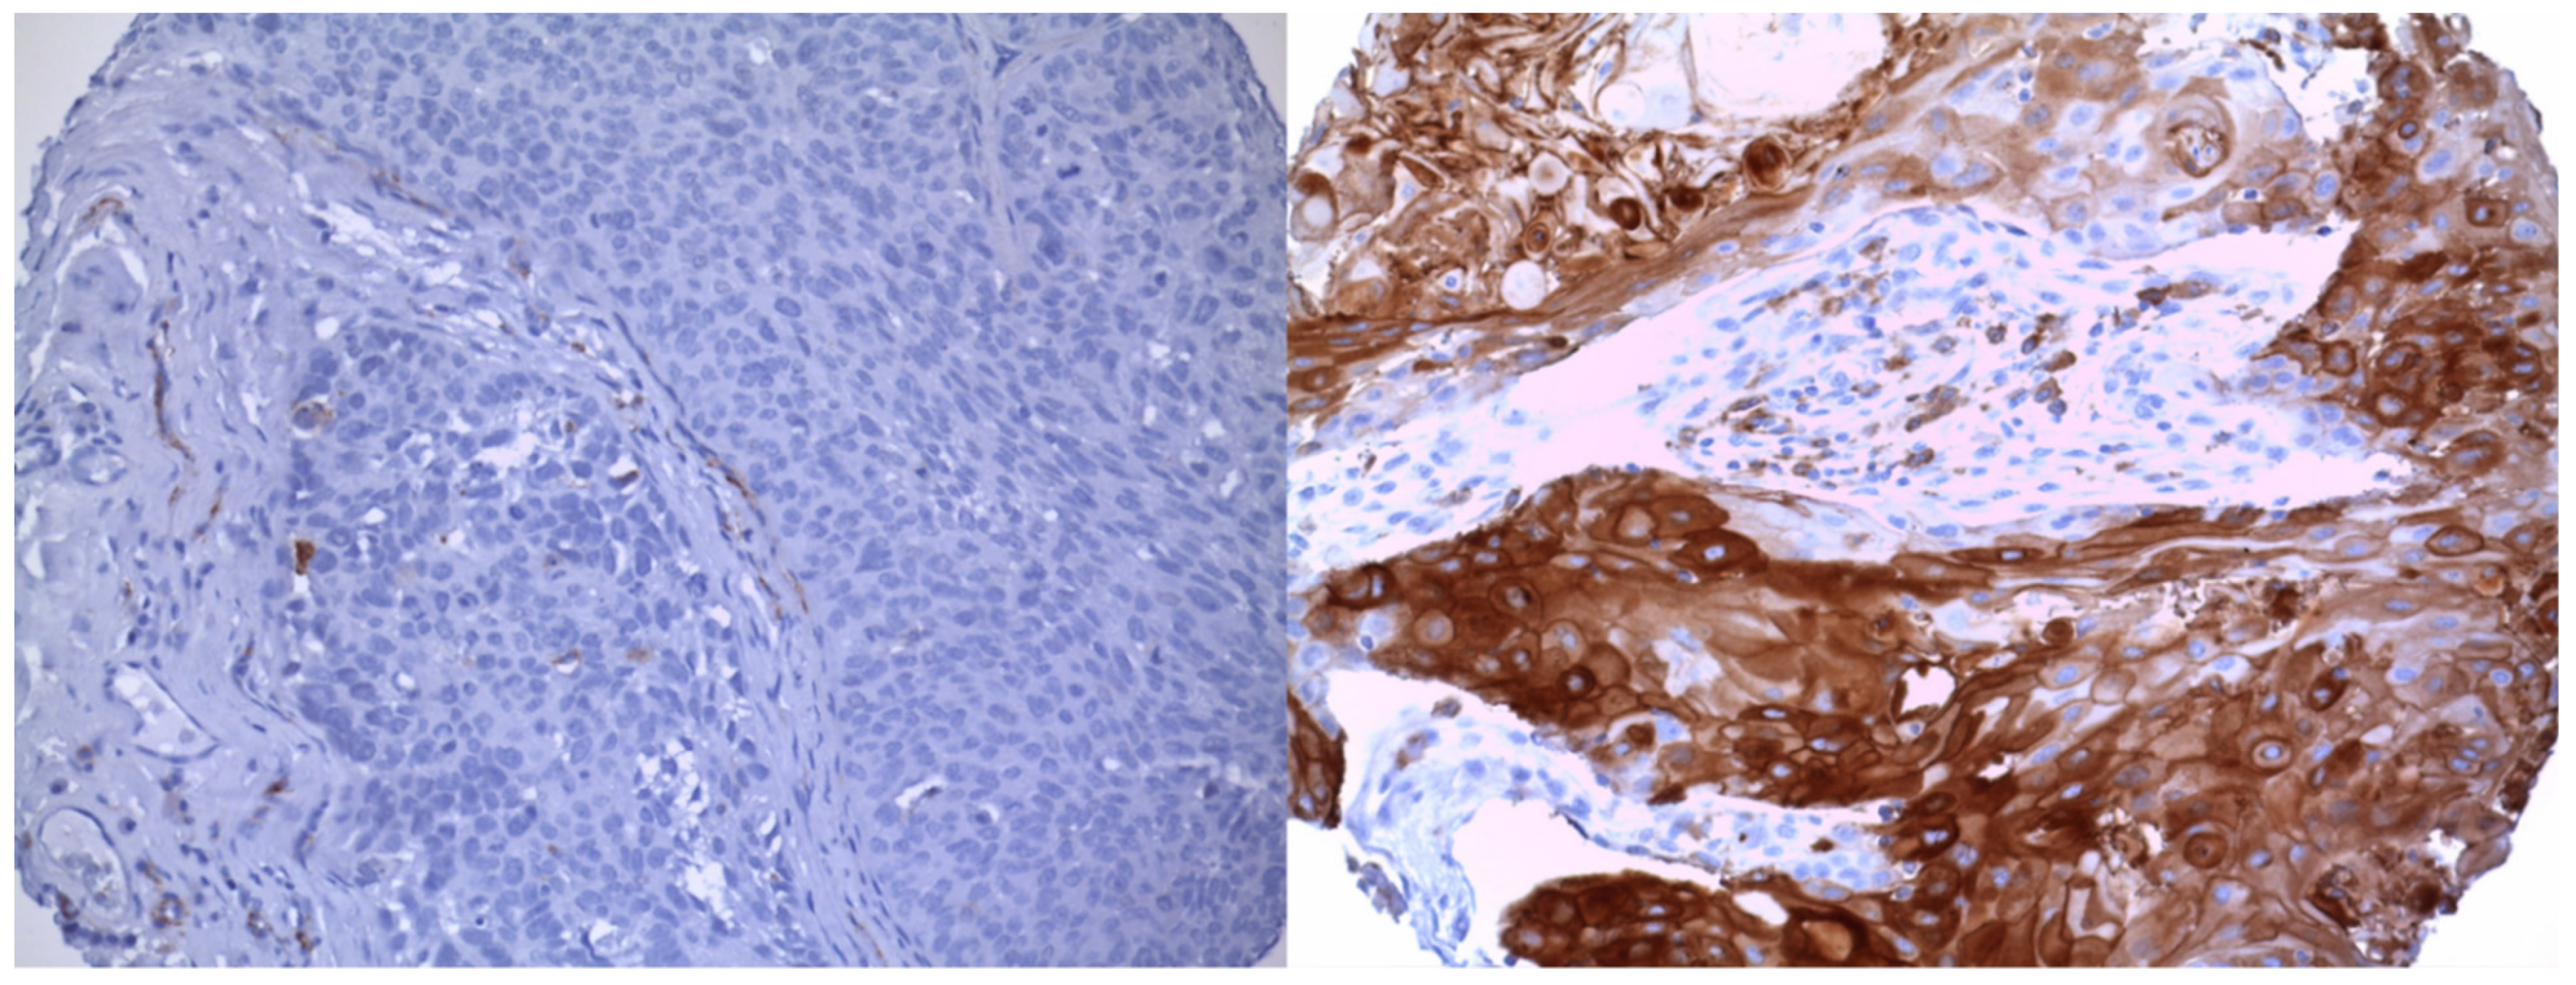

2.3. Immunohistochemistry

| Pretreatment | Heat Treatment with p ProTaqs EDTA Buffer 1 mM pH 8.0 (Fa.Quartett, 400500192) |

| Incubation | Incubation with primary antibody (CD36, (mouse monoclonal, clone OTI3F4)), 60 min RT, dilution 1:50 |

| Detection system | ImmPRESS Anti-Mouse IgG Polymer Kit (Fa.Vector, MP-7402) |

| Chromogen | DAB + (Fa.Agilent Technologies, K3468) |

| Counterstaining | Hematoxylin Gill’s Formula (Fa.Vector, H-3401) |